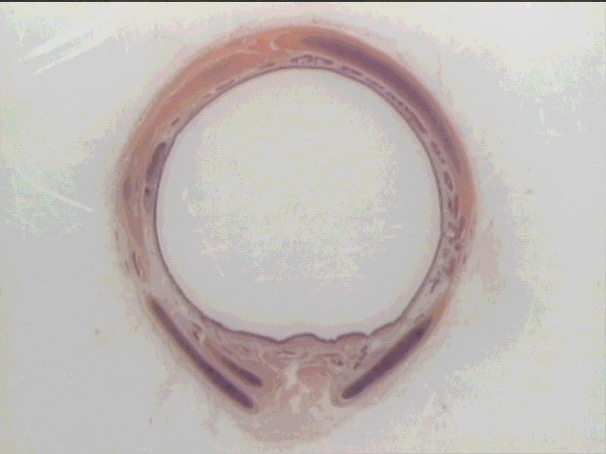

hyaline cartilage rings

C-shaped

c/s trachea

C-shaped hyaline cartilage

trachea

PCCE

cartilage rings